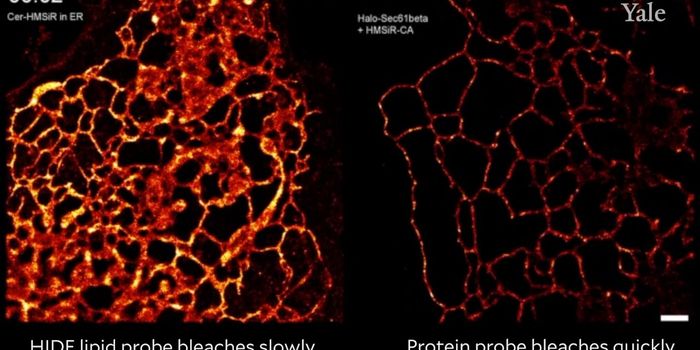

OCT 19, 2017VideosThe field of microbiology has come a long way in the development of instrumentation that allows us to view objects and a ...